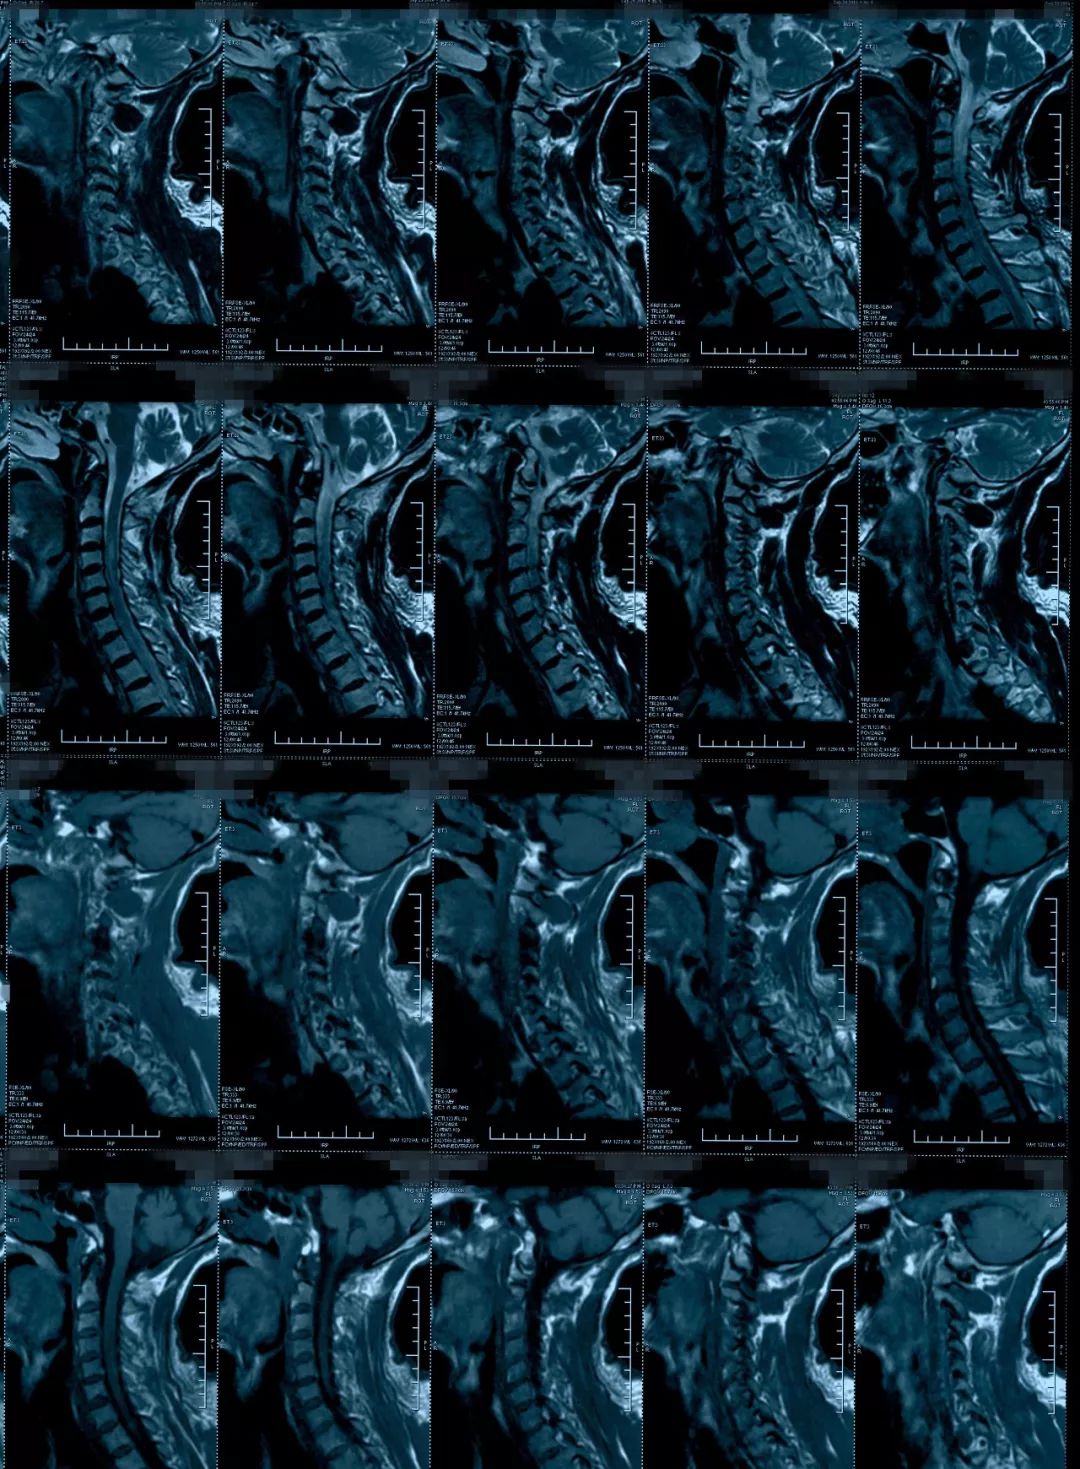

这个病人转到我们科的时候,影像上表现椎管狭窄,脊髓有长阶段的脊髓水肿信号,有黄韧带增厚,后方的间盘有轻度突出,骨质增生等等。

治疗前影像学资料